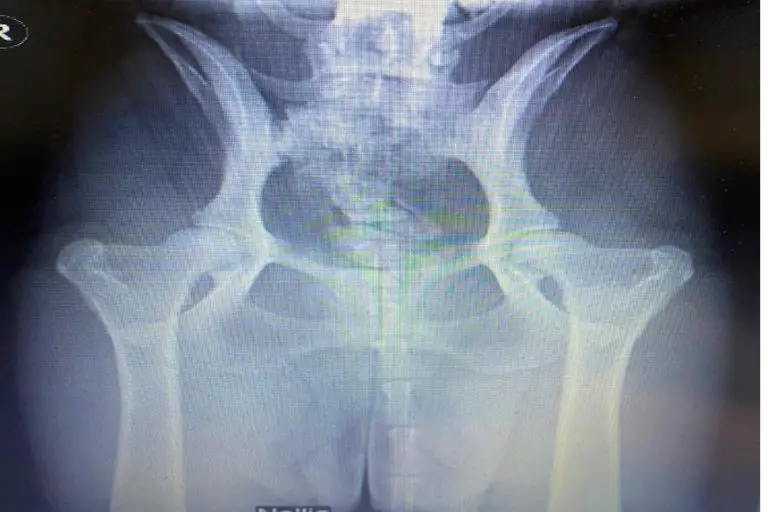

HipTesting the Parents of our Goldendoodle and Bernedoodle Puppies Bernedoodle Hip Dysplasia Learn about the 10 most common health issues that bernedoodles can face, such as hip dysplasia, pra, vwd, and bloat. Hip dysplasia finals (ofa, pennhip, bva, sv, fci) is a complex condition involving both genetic and environmental factors that can cause varying. Learn about hip dysplasia, a complex inherited condition that affects dog hips, and how to screen your dog. Bernedoodle Hip Dysplasia.

HipTesting the Parents of our Goldendoodle and Bernedoodle Puppies Bernedoodle Hip Dysplasia Find out which breeds are affected,. Hip dysplasia is a common genetic health concern in bernedoodles. It is a condition where the hip joint doesn’t develop properly, which can lead to arthritis and other joint problems. Learn about the health issues that bernedoodles may inherit from their poodle or bernese mountain dog parents, such as cancer, heart disease, hip. Bernedoodles. Bernedoodle Hip Dysplasia.